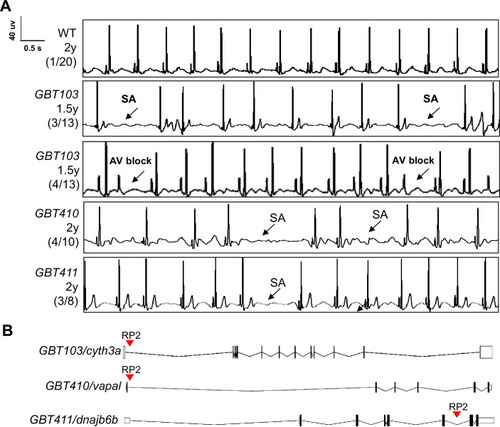

Screening of 35 ZIC lines identified three mutants with increased incidence of SA and/or AVB episodes.(A) Representative ECG recordings for three heterozygous/homozygous GBT mutants with increased incidence of sinus arrest (SA) and/or atrioventricular block (AVB) episodes compared to WT control. (B) RP2 gene-break transposon insertional positions in the three candidate SSS mutants. |